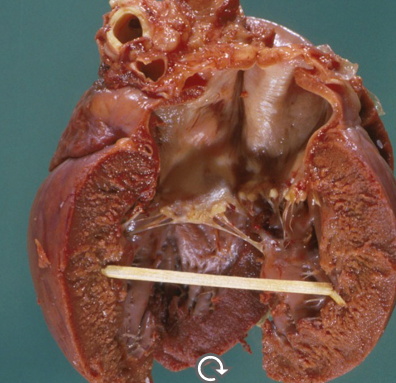

How does dilated cardiomyopathy present grossly?

Biventricular dilation

White thickened endocardium

Walls are normal, may be thinner

Increased heart weight (more than 1% of BW)